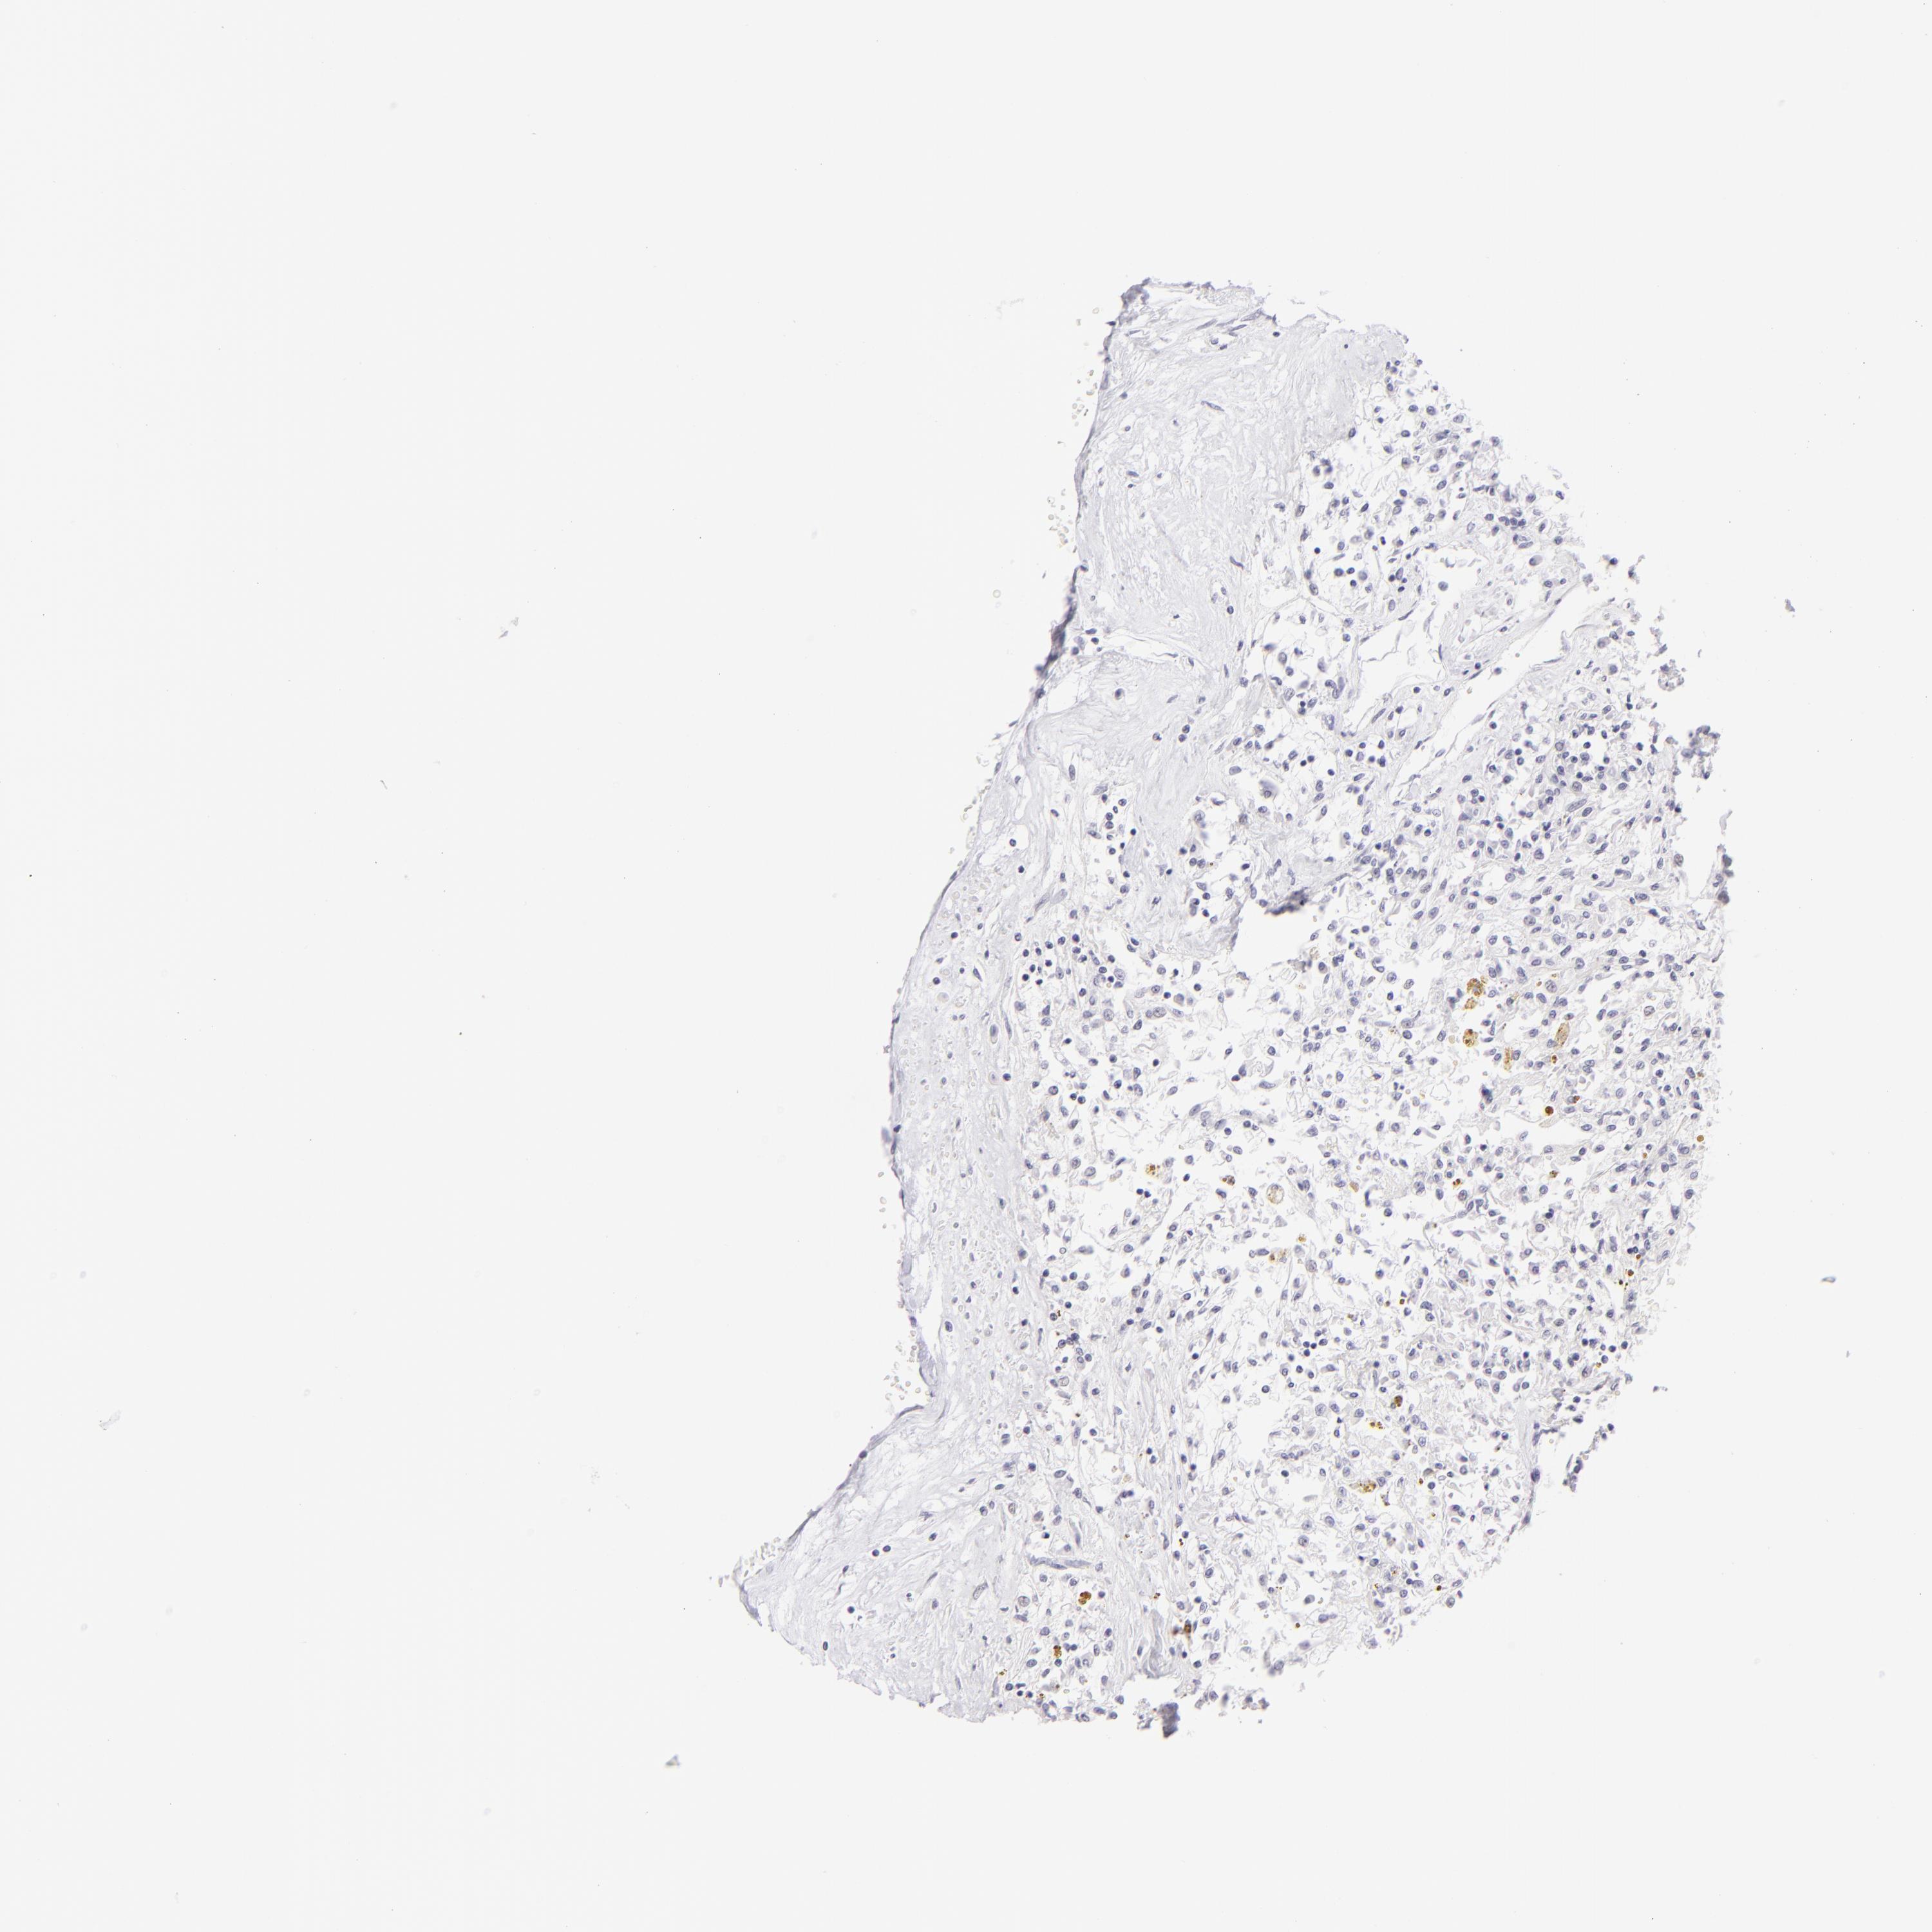

KIDNEY RENAL CLEAR CELL CARCINOMA (VALIDATION) - Interactive survival scatter ploti

The Survival Scatter plot shows the clinical status (i.e. dead or alive) for all individuals in the patient cohort, based on the same data that underlies the corresponding Kaplan-Meier plots. Patients that are alive at last time for follow-up are shown in blue and patients who have died during the study are shown in red.

The x-axis shows the expression levels (FPKM) of the investigated gene in the tumor tissue at the time of diagnosis. The y-axis shows the follow-up time after diagnosis (years). Both axes are complimented with kernel density curves demonstrating the data density over the axes. The top density plot shows the expression levels (FPKM) distribution among dead (red) and alive patients (blue). The right density plot shows the data density of the survived years of dead patients with high and low expression levels respectively, stratified using the cutoff indicated by the vertical dashed line through the Survival Scatter plot. This cutoff is automatically defined based on the FPKM cutoff that minimizes the p-score. The cutoff can be changed by dragging the vertical line or by entering a cutoff value in the square labeled "Current cut-off".

Under the Survival Scatter plot the p-score landscape (black curve; left axis) is shown together with dead median separation (red curve; right axis). Dead median separation is the difference in median mRNA expression between patients who have died with high and low expression, respectively. It is calculated as follows: median FPKM expression of dead patients with high expression - median FPKM expression of dead patients with low expression. This is intended to aid the user in visually exploring custom cutoffs and the associated p-scores and dead median separation.

Individual patient data is displayed and can be filtered by clicking on one or more of the category buttons on the top of the page. Categories describing expression level and patient information include: high, low, alive, dead, female, male and tumor stages. The scale of the x-axis can be toggled between linear and log-scale by clicking on the "x log" button. Mouse-over function shows TCGA ID, patient information and mRNA expression (FPKM) for each patient.

& Survival analysisi

Kaplan-Meier plots summarize results from analysis of correlation between mRNA expression level and patient survival. Patients were divided based on level of expression into one of the two groups "low" (under cut off) or "high" (over cut off). X-axis shows time for survival (years) and y-axis shows the probability of survival, where 1.0 corresponds to 100 percent.

FCER2 is not prognostic in Kidney Renal Clear Cell Carcinoma (validation)

TCGA RNA samplesi

RNA-seq data is reported as average FPKM (number Fragments Per Kilobase of exon per Million reads), generated by the The Cancer Genome Atlas (TCGA) .

Normal distribution across the dataset is visualized with box plots, shown as median and 25th and 75th percentiles. Points are displayed as outliers if they are above or below 1.5 times the interquartile range. FPKM values of the individual samples are presented next to the box plot.

Average pTPM 0.2

Number of samples 100